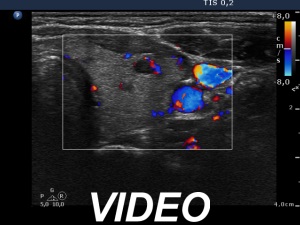

Follow-up examination 8 months after the previous visit (second row of images):

Clinical presentation. The previous symptoms were resolved after administering antacids. Four weeks prior to the present examination the patient noticed an increased heart rate and other complaints suggesting relapse of the hyperthyroidism. In contrast with the first episode of Graves' disease, thyroid associated ophthalmopathy has appeared.

Palpation: unchanged.

Laboratory examination: TSH 0.001 mIU/L, FT4 43.1 pM/L.

Ultrasonography. The thyroid became more hypoechogenic, the echogenicity index has increased to 50% as had the vascularization. Multiple hypoechogenic areas have appeared, none of them fit to a nodule in a pathological sense.

Suggestion: daily 20 mg methimazole and surgery after restoration of FT4-level.